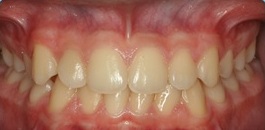

Documentação composta de radiografias, fotografias, modelos e análises cefalométricas com o objetivo de realizar um estudo detalhada da interrelação das estruturas dento faciais do paciente. Possibilitando a escolha do tratamento correto para o mesmo. Indicação: Tratamentos Ortodônticos e Ortopédicos.